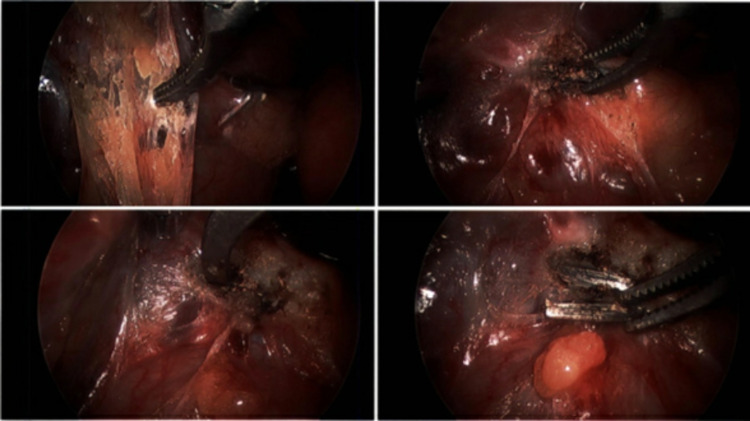

Considering the high possibility of nickel surgical clips retained during her cholecystectomy causing her symptoms, the decision was made to remove the surgical clips. A week after her visit, the patient had a diagnostic laparoscopy and removal of six metal surgical clips from her RUQ via fluoroscopic guidance (Figure11).

Diagnostic laparoscopy evaluation with fluoroscopic guidance was performed to locate the positioning of six metal surgical clips.

Six metal (nickel) surgical clips were identified and removed from the right upper quadrant with the assistance of fluoroscopic guidance.